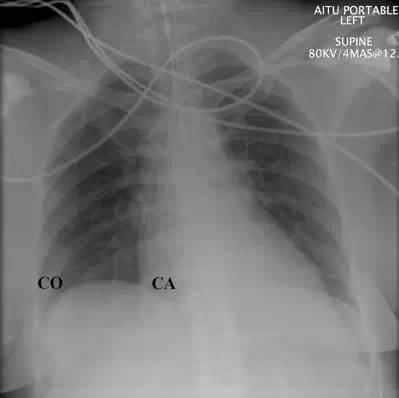

自发性气胸胸片

自发性气胸胸片,自发性气胸

正常胸片 b.右侧肺气肿 c.纵隔肿瘤 d.右侧气胸 e.纵隔气肿

自发性气胸

气胸胸片

气胸x线胸片图解